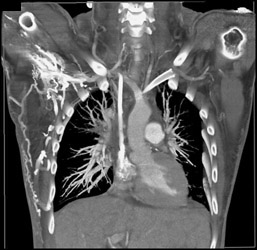

Diagnosis

Normal CTA